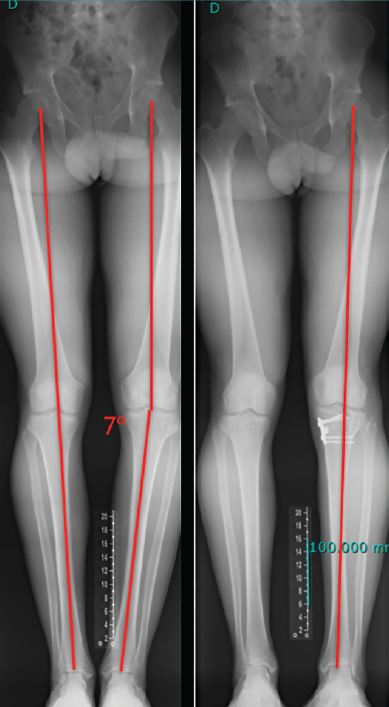

El estudio radiológico recomendado debería incluir proyecciones anteroposteriores y laterales, axiales de rótula, telemétricas de la extremidad inferior y también en posición de Schuss (en carga y con unos 30° de flexión de la rodilla). La radiología simple va a permitir identificar qué técnica quirúrgica se realizó inicialmente y qué material se utilizó para la fijación (Figura 1). La proyección en Schuss permite observar si existen cambios degenerativos en los compartimentos femorotibial interno o externo de la rodilla de forma más precisa que con la radiología simple en decúbito supino. Finalmente, la radiografía telemétrica de las extremidades inferiores va a permitir conocer el eje mecánico de la extremidad. La existencia de deformidades en el plano coronal se ha asociado a un incremento de la solicitación mecánica del LCA y también del riesgo de rotura de la plastia (Figura 2)(21).

Figura 2. Paciente de 21 años con antecedente de reconstrucción anatómica del ligamento cruzado anterior (LCA) y ángulo posteroexterno que requirió cirugía correctiva de un genu varo de 7° después de fracasar la reconstrucción ligamentosa.

Independientemente de las deformidades en el plano axial, las deformidades en el plano coronal, sobre todo el genu varo, se han relacionado también con un incremento de las solicitaciones mecánicas sobre el LCA y secundariamente como factor de riesgo de rotura(45,46).